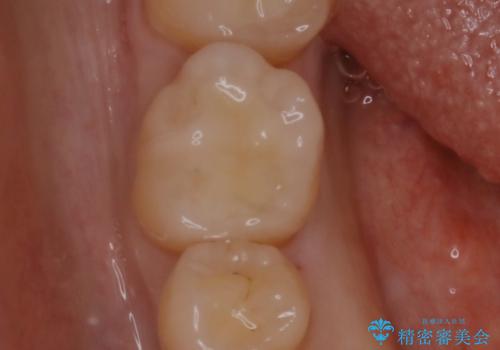

腫れもなくなり、見た目もきれいになったため、右上もご希望されて計3本の歯を治療しました。患者様には大変満足して頂きました。

左上で効果を実感して頂き、その後右上もご希望されました。合計3本の歯を治療しました。